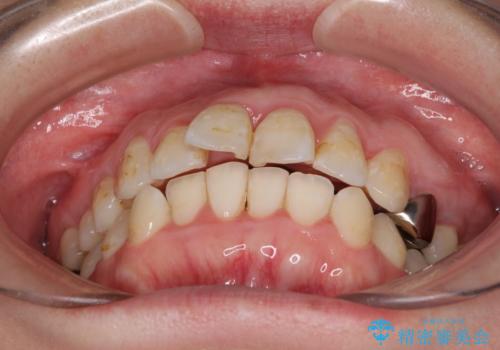

- 出っ歯と口の閉じにくさ、デコボコを気にして来院された患者様です。

口元の突出感を改善するため、上下左右第一小臼歯4本の抜歯を行い、ワイヤー装置による矯正治療を行うこととしました。

上下前歯の距離が大きかったため、上下の歯が接触するまでに時間がかかりました。

それでも目安である2年半で終えることができ、患者様には大変満足していただけました。